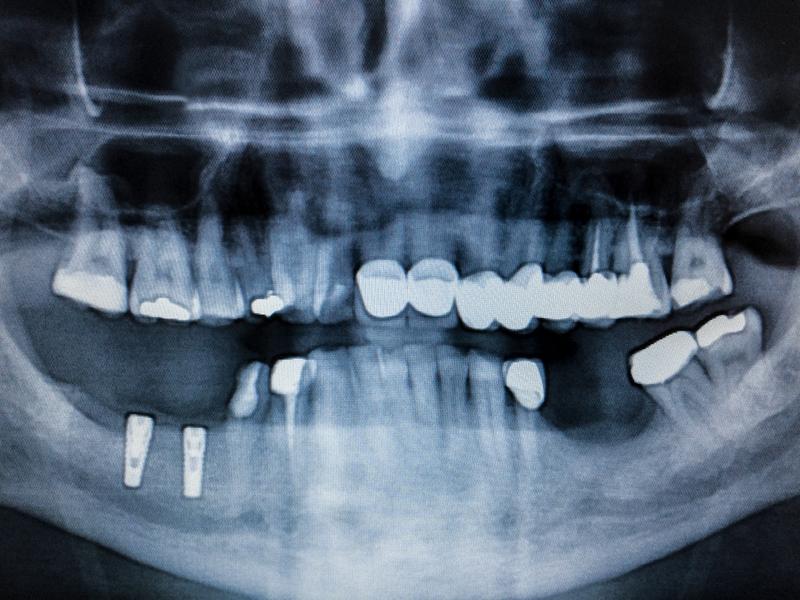

La periodontitis es una inflamación e infección de las encías en estado avanzado que hace que el hueso y los ligamentos que soportan el diente se pierdan, haciendo que el mismo se debilite hasta caerse.

En un principio el paciente presentará gingivitis, una inflamación de las encías producida cuando la placa y el sarro se acumula entre el diente y la encía sin ser extraídos adecuadamente. Este proceso inflamatorio va avanzado y, de no se tratado a tiempo con medidas como la adecuada higiene bucal, el uso diario de hilo dental, y las limpiezas dentales profesionales una o dos veces al año, la inflamación irá creando bolsas de sarro y placa entre la encía y el diente que acabarán por afectar la los tejidos de soporte y el hueso del diente. Esto hará que los dientes se muevan con facilidad y estén tan debilitados que comiencen a caer, en ocasiones no caen por si solos pero la debilidad hace que sea necesario extraerlos pues han dejado de cumplir su adecuada función.

La acumulación de placa bacteriana es la causa de esta condición que puede deberse a:

• Una mala higiene dental: falta de cepillado, no usar el hilo dental o no visitar al dentista para las limpiezas profesionales.

• Una mayor predisposición genética de acumular placa dental, lo que podría aumentar la posibilidad de sufrir de esta condición.

• Sufrir de bruxismo, es decir apretar los dientes de forma consciente o inconsciente. Esto puede hacer que la encía retroceda aumentando el riesgo de sufrir gingivitis y periodontitis.

• Padecer de diabetes, los pacientes con esta condición son más propensos a esta enfermedad.

• Tener el sistema inmune debilitado por condiciones como el cáncer, la quimioterapia, el VIH o enfermedades autoinmunes.